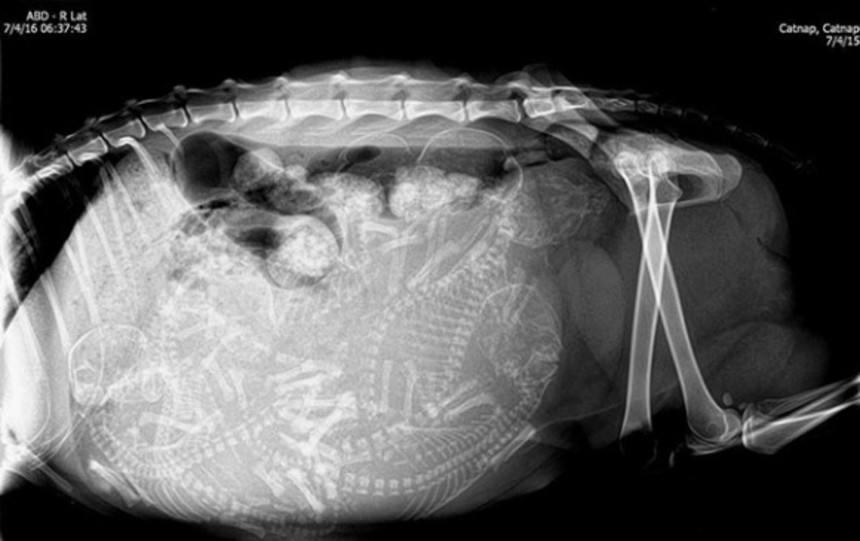

この画像を大きなサイズで見る5. 猫

出産直前に、お母さんのお腹の中に何匹の赤ちゃんがいるかの確認のためのレントゲンだよ。

何匹いるか確認しておかないと、死産で残ってしまったりしたらお母さんの体が危険でしょ?

って元スレのコメに書いてあったよ。

猫お腹にいっぱいおる

人間は基本一人だけど、三匹四匹まとめてお腹に入れてるのはレントゲンで見るとやっぱ驚く。

結構ごちゃごちゃっと入ってんのね…

猫とかアライグマのは整頓してあげたい